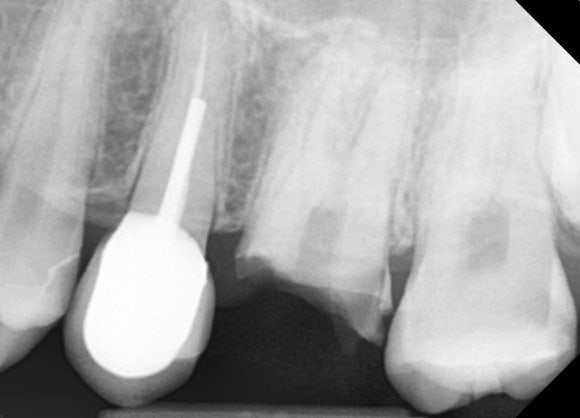

엑스레이를 노려보니

생각보다 뿌리의 길이가 깁니다.

잇몸도 건강하고 두꺼워보입니다.

그럴땐 치은절제술을 통해 뿌리의 일부를 노출시킵니다.

위 사진은 충치를 모두 제거하고 치은절제술로 뿌리를 노출시킨 사진입니다.

치아 가운데에 동그랗고 불투명한 것이 보입니다.

포스트의 단면입니다.

흰색은 레진입니다.

뿌리 위에 레진을 올리고, 이를 유지하기 위해 포스트를 삽입했다고 이해하시면 됩니다.